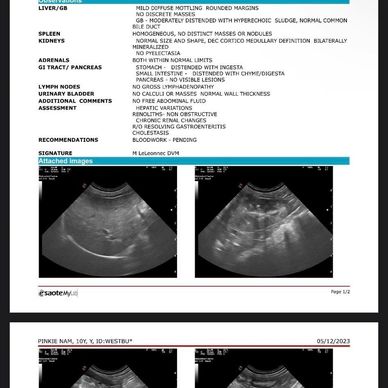

I apologize in advance for the long post. My dog is 10.5 years old and she has had pancreatitis flare ups in the past. I brought her in because she wasn’t eating unless it was from my hand, vomited bile, and just seemed a bit more lethargic in general. They were able to run bloodwork and an ultrasound and I have posted the results below. We sadly live in an area where there are practically no holistic vets within an hour of us, other than house call acupuncture vets. Her traditional vet stated that Pinkie had stones in her kidneys but not in her bladder and that it is not a concern, which I have since learned otherwise. She also diagnosed Pinkie with kidney disease with only the ultrasound before the bloodwork even came back. She does not have symptoms of kidney issues- no excess drinking, no excess urinating, etc. which is why it was a complete shock when her vet mentioned kidney disease. She did not give me a protocol to follow but after doing some research, I’m wondering if you approve of what I came up with- I read about lysimachia-3, Dang Gui and Peony Support Formula, milk thistle, calcium citrate, rhemannia-8 and I’m wondering which ones you think are appropriate in this case. She will be on a real food diet, although I’m having trouble finding the right one. I’m looking at one that has a phosphorous content of 0.43 DMB- is that okay? I am also planning on geting her acupuncture as I have read the various benefits of it. I read a lot of previous posts from this group and I’m also wondering if the calcium oxalate stones can be dissolved and if kidney disease can be reversed as I know traditional vets believe neither is possible. But I read about Leslie Bean’s success with her dogs and their calcium oxalate stones. Her blood work shows an increase in BUN and BUN/creatinine ratio but with normal creatinine levels. Her SDMA levels are also in normal range and I’m wondering if her ultrasound and blood work are indicative of kidney disease like her vet stated. Thank you for everything!

Dr. Steve's Advice - the kidney issues are very early, so there is not much to panic about. Also, the report is unclear whether they saw mineralization in the kidneys, which indicates a blood flow issue, or stones. The description suggests mineralization, and the assessment suggests stones. The ultrasounds are too small for me to tell myself. Please get clarification from your vet and/or ultrasonographer.

Meanwhile, to support kidney blood flow to lower BUN, and to help prevent pancreatitis, I would suggest you get Glehnia and Rehmannia from Kan Essentials (often available on Amazon in the US). It should help settle the stomach, too.

I applaud your decision to feed real food. I don't see the need to worry at all about phosphorus levels yet. Increased phosphorus is really only a concern in some dogs, and at much later stages of the disease. Any meat-and-vegetable diet will probably work for now to correct the vascular issues that are compromising renal blood flow.